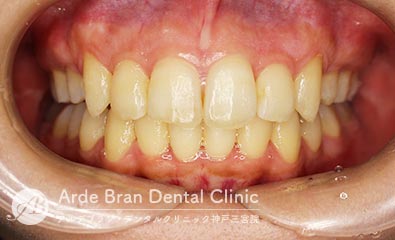

- 叢生/歯のがたつき(20代男性 治療期間10カ月)

- 上下の前歯の歯のがたつきを治したいとの事でご来院されました。なるべく目立たない装置をご希望されたため、インビザラインにて治療を行いました。中等度の叢生量だったため、インビザラインモデレート(枚数26枚)にて治療を行う事が出来ました。短期間で費用も可能な限り抑えつつ治療を完了する事が出来ました。

- 治療前

- 治療後

| 装置名 | インビザライン(マウスピース矯正) |

| 抜歯非抜歯 | 非抜歯 |

| 治療期間 | 10カ月 |

| 費用 | インビザラインモデレート(上下)60万円+TAX 再印象(3万円+TAX)×1回 |